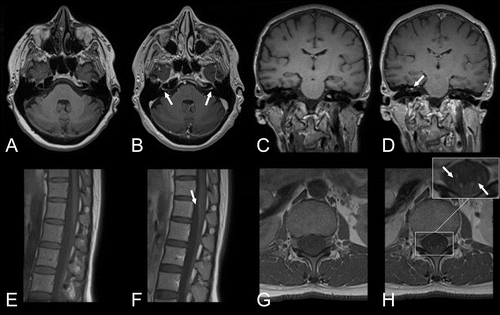

Les neuroradiologues ont une formation en radiologie diagnostique pour étudier diverses maladies telles que les accidents vasculaires cérébraux, les maladies démyélinisantes, les maladies neurodégénératives, les tumeurs cérébrales, les cancers de la tête et du cou, les maladies neurovasculaires, les traumatismes, les douleurs dorsales et d'autres maladies neurologiques.

Les principales modalités d'imagerie sont la tomodensitométrie (Scanner) et l'imagerie par résonance magnétique (IRM).